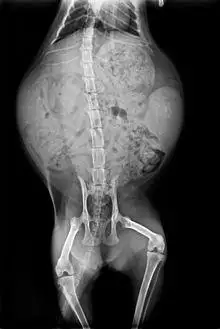

Radiography of a pregnant cat. The skeletons of two fetuses are visible on the left and right of the uterus.